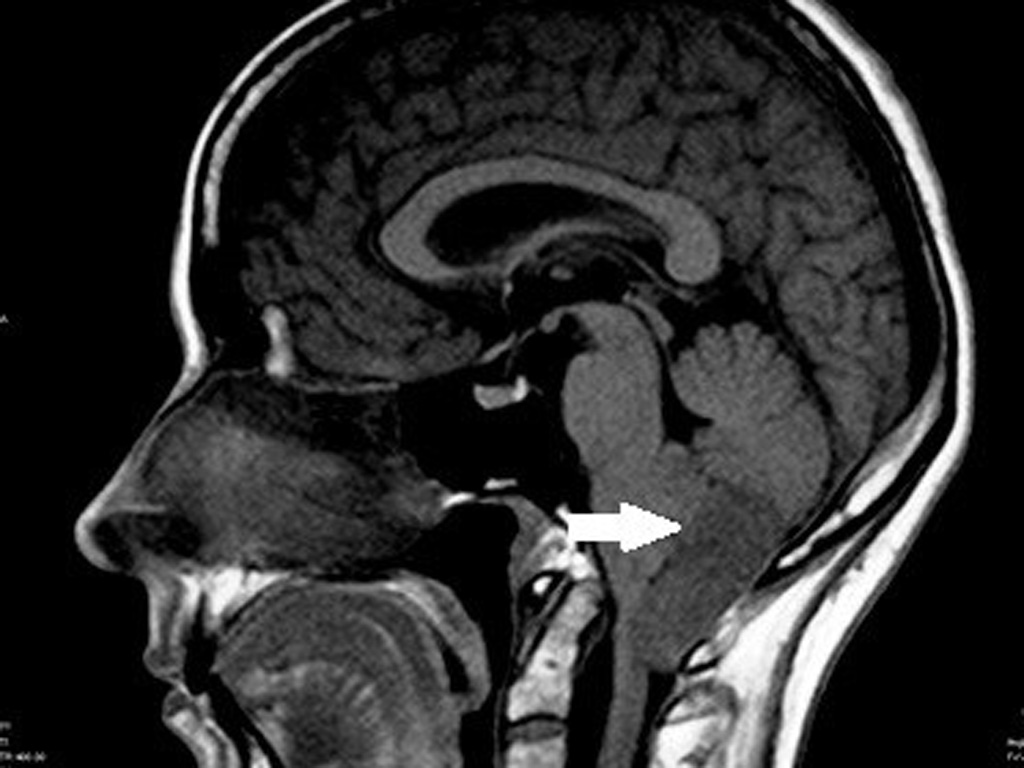

- инфратенториальные (субтенториальные) – расположенные в задней черепной ямке (Зчя), задней области головного мозга, где находятся мозжечок, ствол мозга и четвёртый желудочек.

Симптомы эпендимомы зависят во многом от её локализации. В случае инфратенториального расположения (например, опухоль находится в 4 желудочке), проявления болезни бывают особенно тяжёлыми.

- МРТ – особенно информативно при обследовании головного мозга. Снимки помогают уточнить размер, структуру и форму новообразования, выяснить состояние сосудов. МРТ безопасно для детей благодаря отсутствию излучения;

При диагностике эпендимому необходимо дифференцировать с субэпендимарной астроцитомой (самой распространённой опухолью в головном мозге, разновидностью глиомы) и невриномой (доброкачественной опухолью с локализацией в области конского хвоста).